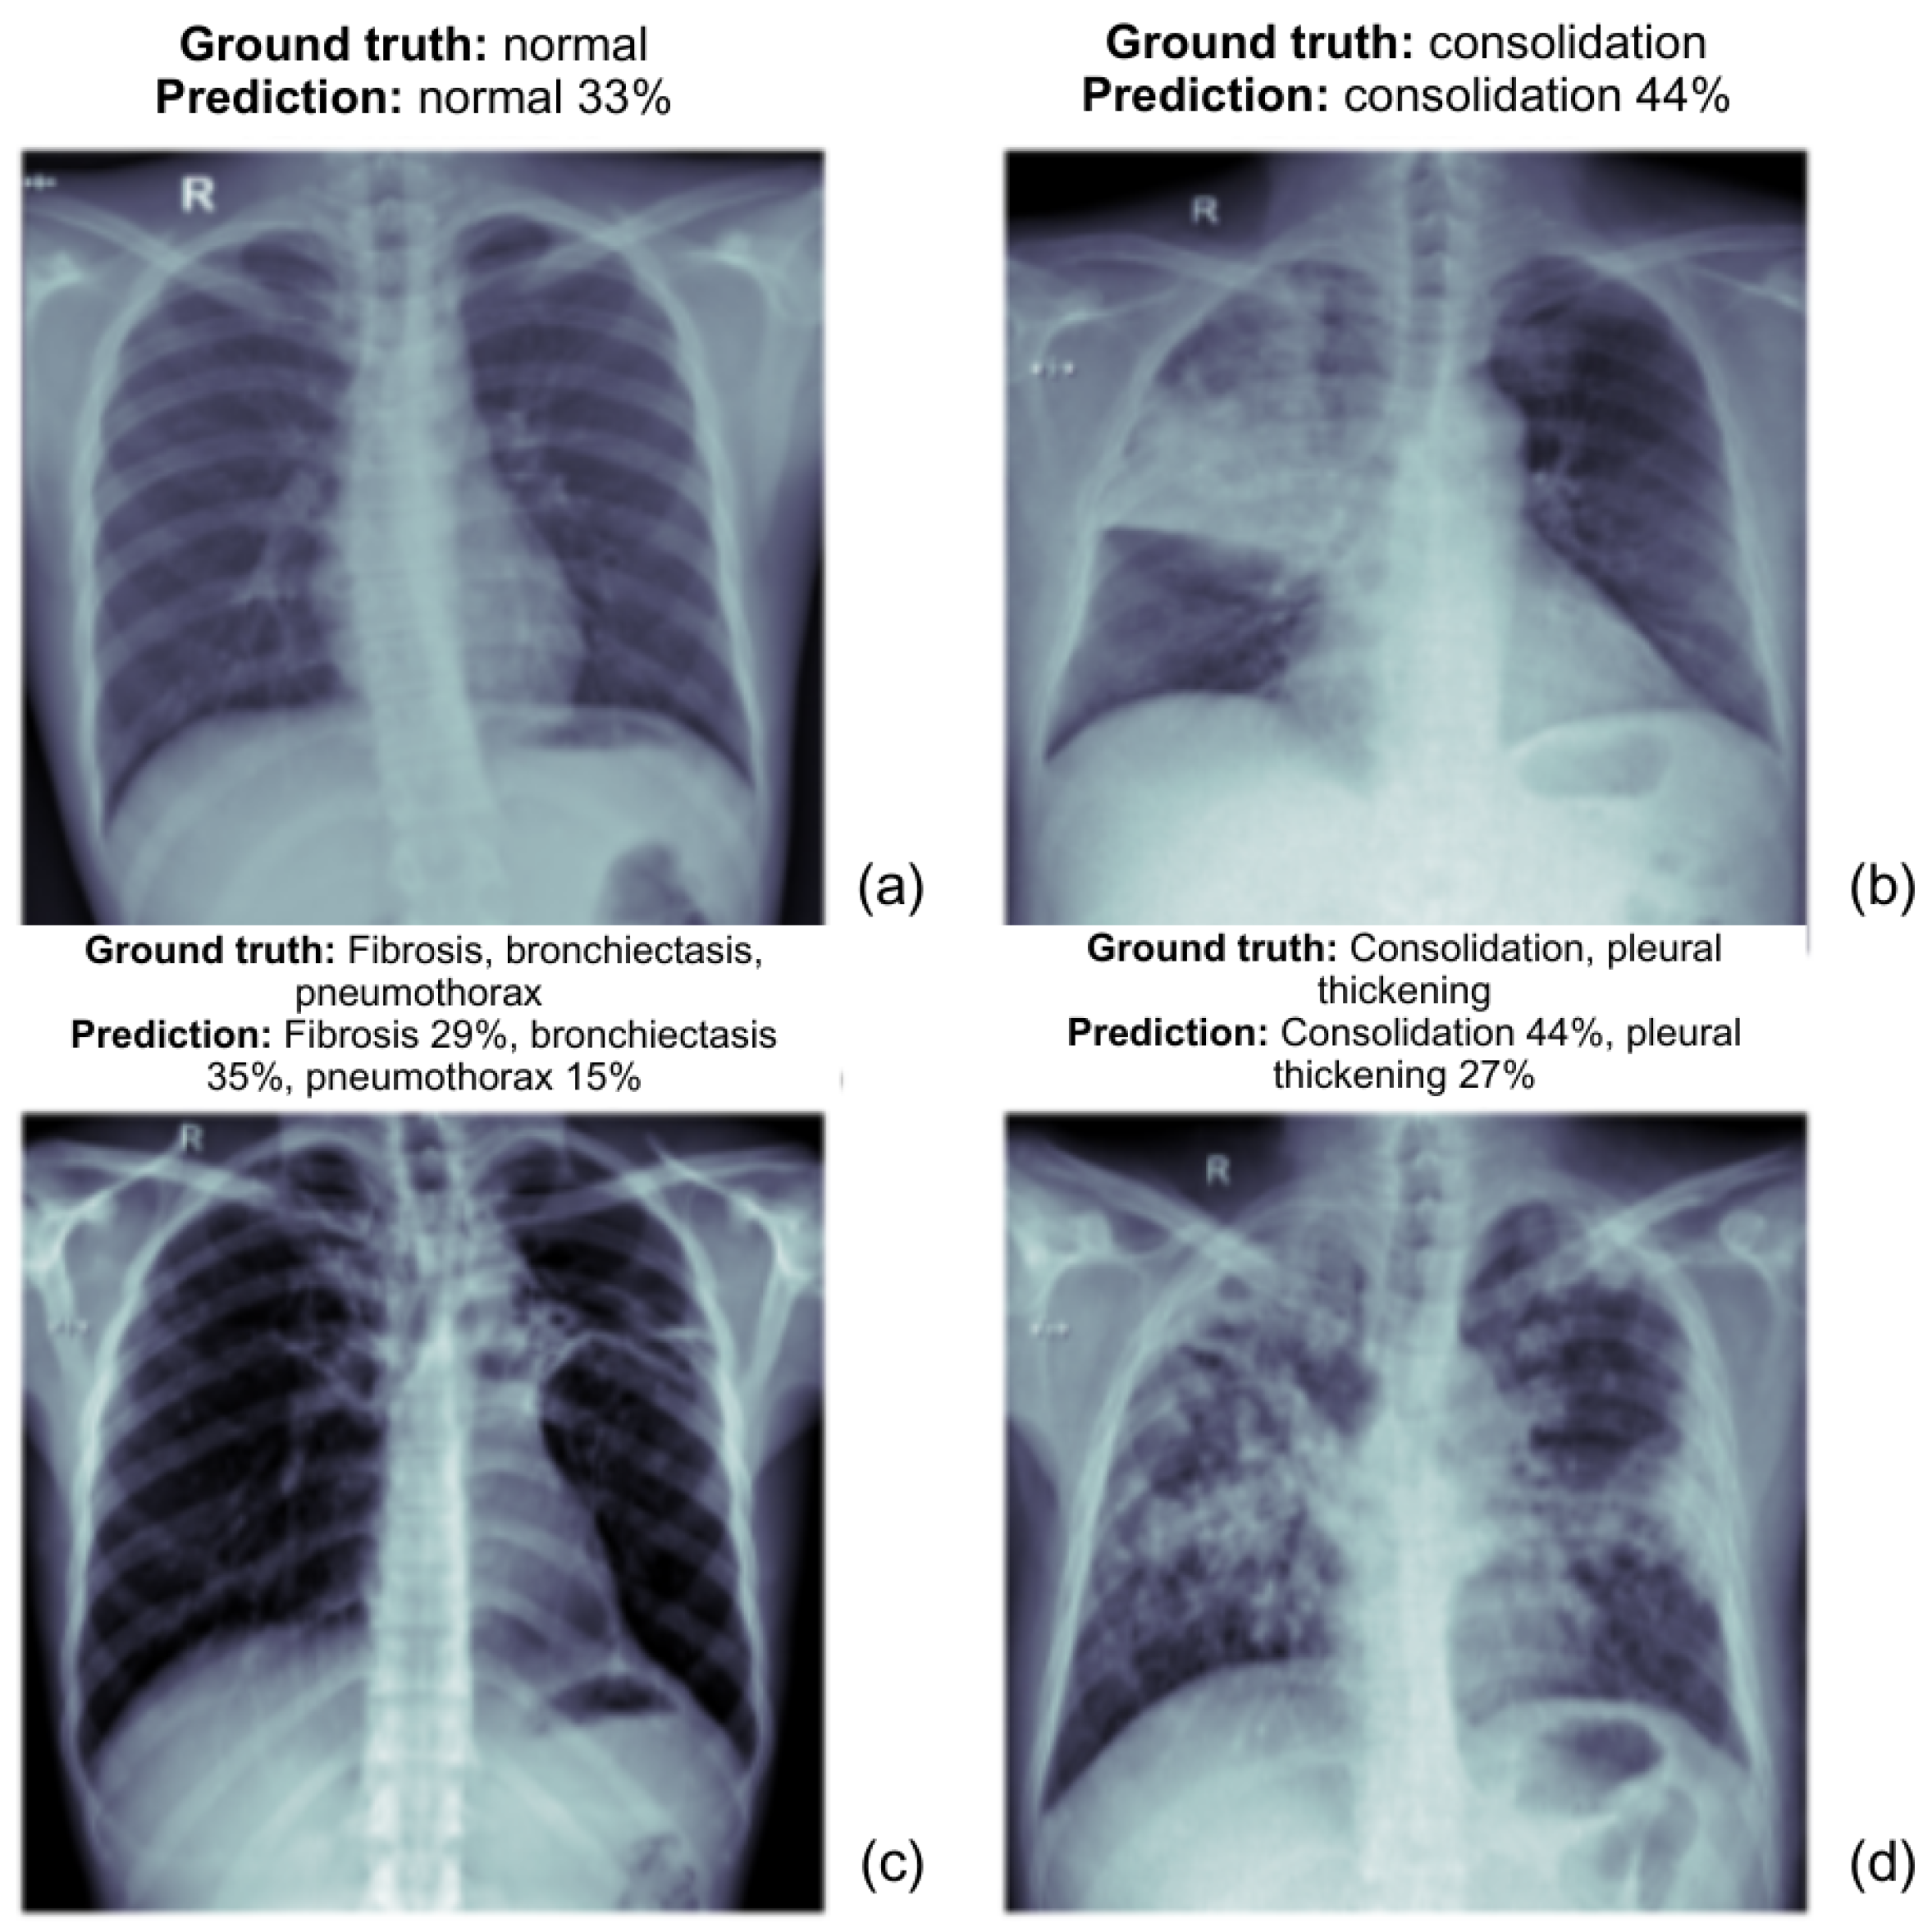

The following images as shown in the Figure 5 present the prediction outcomes from the EfficientNetV2L model. Each image includes a comparison between the actual diagnosis and the predicted diagnosis, along with the model’s confidence level for each predicted label. This analysis demonstrates the ability of both models to detect various TB-related abnormalities from chest X-ray (CXR) images.

Figure 5.

EfficientNetV2L model prediction results for normal and TB anomalies, with confidence score for each label. Each subfigure represents a chest X-ray (CXR) image with the corresponding ground truth and model predictions.

- (a)

- The ground truth is normal, and the model correctly predicts it with a confidence of 33%. The prediction aligns with the actual diagnosis, though the confidence could be higher.

- (b)

- The ground truth is consolidation and the model predicts it with 44% confidence. The model correctly identifies the abnormality, demonstrating its potential in recognizing consolidation.

- (c)

- The ground truth includes fibrosis, bronchiectasis, and pneumothorax. The model predicts these conditions with fibrosis 29%, bronchiectasis 35%, and pneumothorax 15%. These predictions reflect a reasonable overlap with the ground truth.

- (d)

- The ground truth includes consolidation and pleural thickening. The model predicts consolidation with 44% confidence and pleural thickening with 27% confidence, which aligns well with the ground truth.